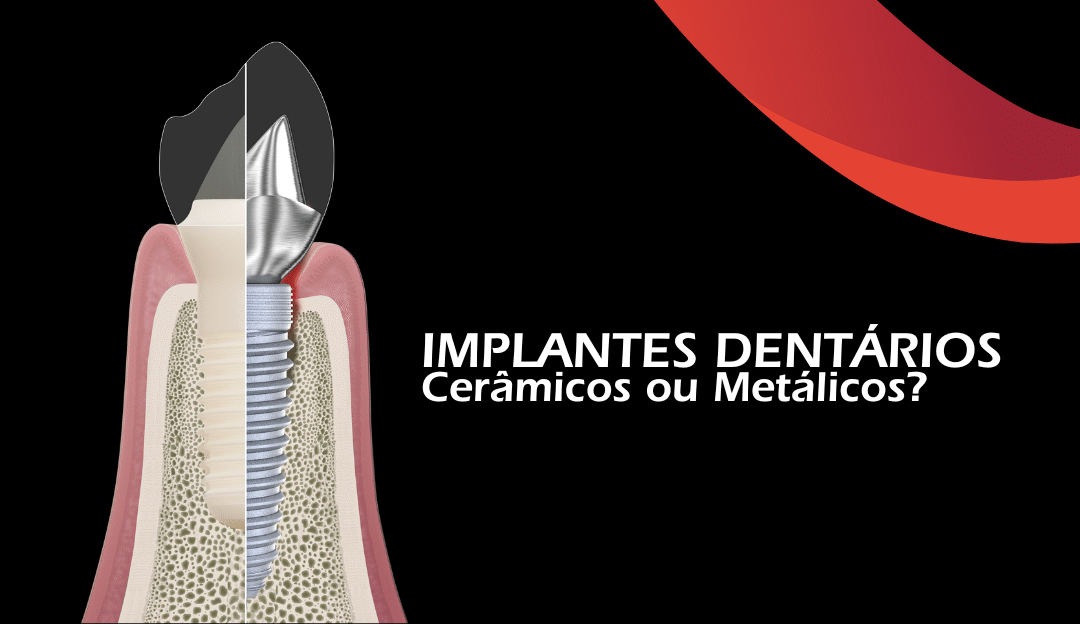

Um implante é uma raiz artificial que serve de base para um novo dente, restaurando a aparência e a função. Mas a grande questão é: que material escolher?

Os implantes cerâmicos de zircónia são, portanto, os implantes do séc. XXI, que mostram boa osseointegração, comparável à do titânio e são mais resistentes à acumulação de placa bacteriana, o que pode reduzir o risco de peri-implantite.